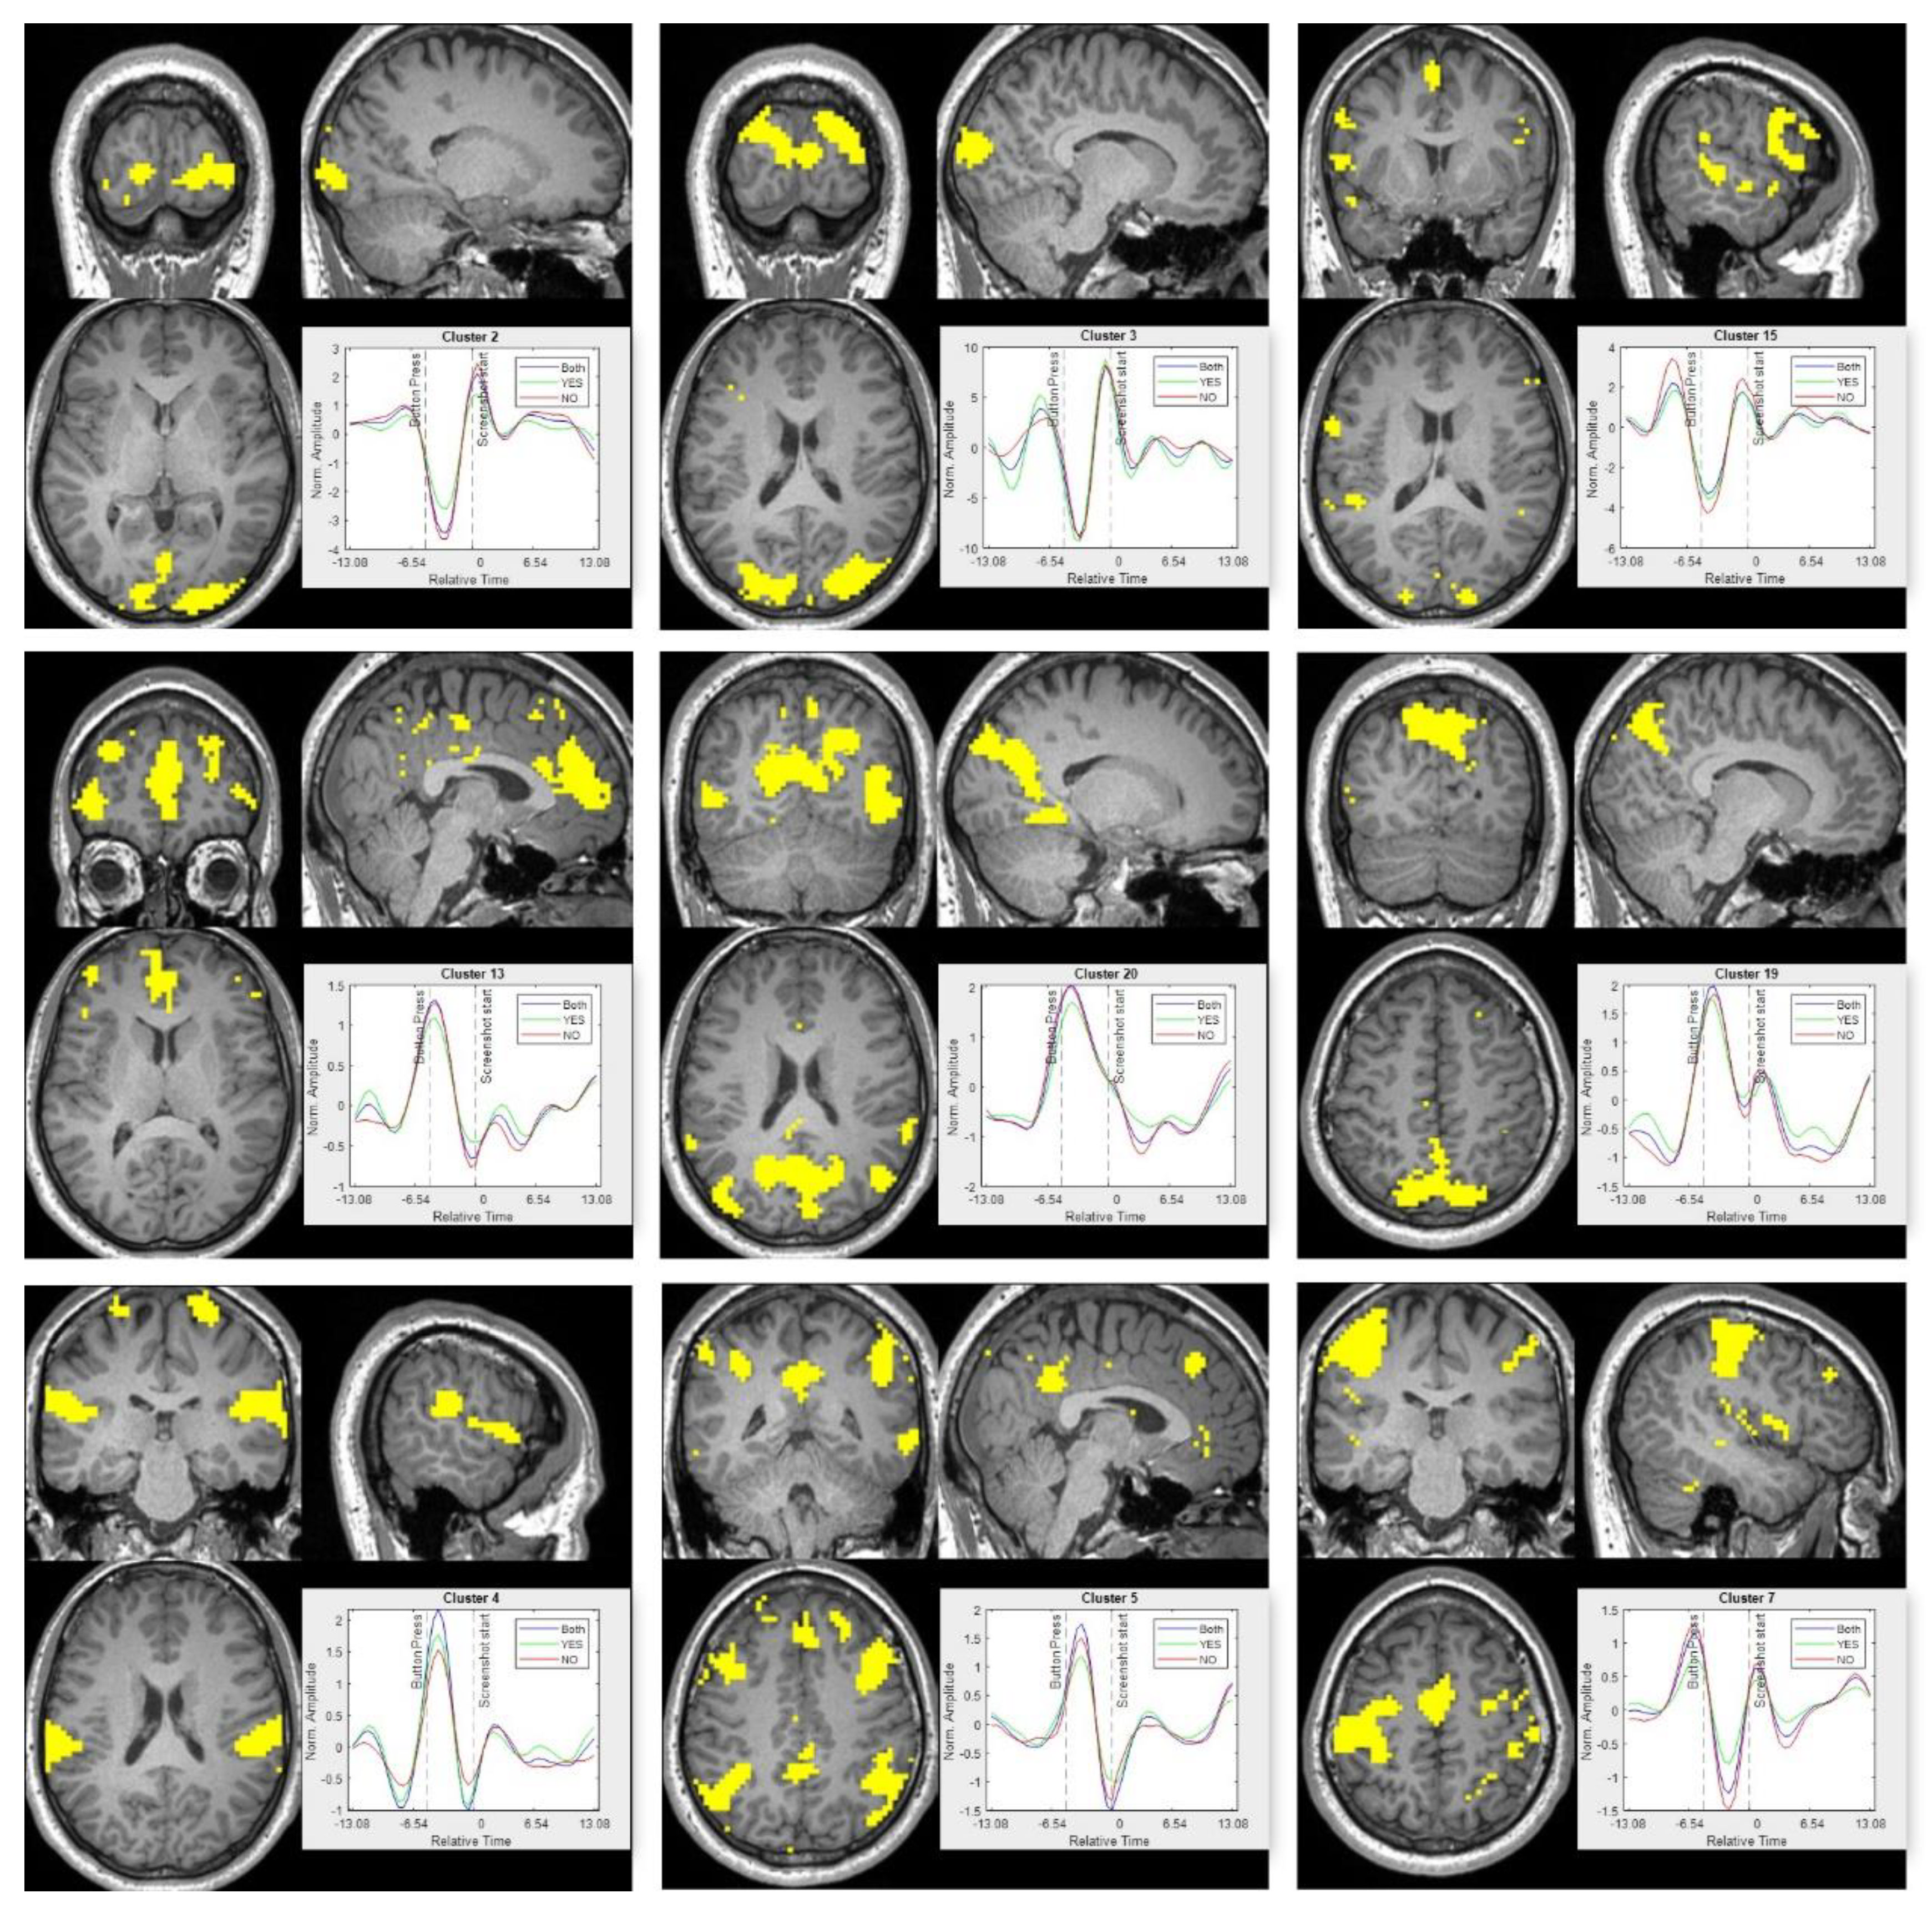

Appendix A.4. K-Means Clusters

The spatial clusters and the corresponding time series for all 20 clusters are shown in Figure A4 and Figure A5, respectively. The spatial clusters are shown for all the apps (irrespective of the response), while the representative time series for all the clusters are shown for all three cases (irrespective of the response, only yes response and only no response to download decision).

Figure A5. Temporal for each of the 20 spatial cluster shown in Figure A4. The response for ‘yes’ apps is shown in green; ‘no’ apps is shown in red and the case for all user decision (both yes and no) is shown in blue. The x-axis represents normalized time that is centered at the beginning of new app (new stimulus), while the y-axis represents the averaged normalized amplitude.

The group-level spatial and temporal results for L1 regularization of the first difference is shown in Figure A8. The solution to the optimization using L1 regularization of the first difference was solved by an iterative process. As discussed in Appendix A.7, a modified pipeline was used to obtain group-level results. The group-level results are very similar to the results obtained using L2 regularization. The temporal smoothing of the pseudo-stimulus may be caused by the averaging of response across all the trials and participants. The positive and negative peaks time locked to the experiment design is observed. The spatial clusters 2 and 3 overlap with the visual cortex regions and the temporal response shows a positive peak at the beginning of the trial. The clusters 19 and 20 overlap with the default mode network and their temporal response peaks during the blanking period (between the button press and beginning of the new trial). As discussed earlier, the default mode network is a task-negative network, and the temporal response for clusters 19 and 20 seems to be following that trend. Spatial cluster 13 overlaps with the brain regions of DLPFC, VMPFC and ACC. The temporal response for cluster 13 peaks towards the end of the decision-making process, which is similar to results observed for L2 regularization and discussed in Section 3 above. The motor cortex overlaps with cluster 7 and the temporal response has a dominant peak towards the end of the trial as observed for results of L2 regularization.

Figure A8. Spatial and temporal results for L1 regularization of the first difference. The spatial maps correspond to k-means clusters. The cluster numbers are indicated on top of the time series subplot. The temporal plot shows the mean response of the clusters to ‘YES’ apps (green), ‘NO’ apps (red) and ‘all’ apps (blue). The temporal response is centered at the beginning of the new trial. The instance of a button press and beginning of new trial is indicated with dotted lines.